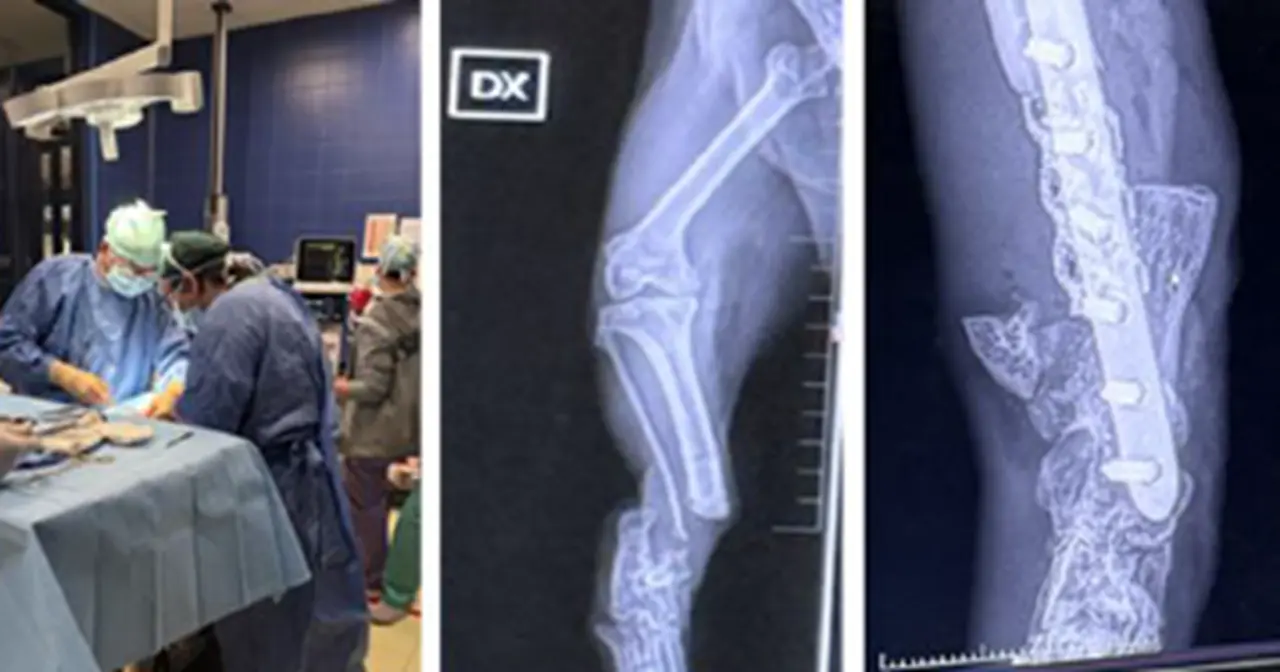

This methodology aims to be applied in both veterinary medicine and human medicine through the scientific excellence of the Department of Precision and Regenerative Medicine and the Ionian Area (DIMEPRE-J), for the regeneration of tendon tissues of muscles, neurons, nerve fibers, as well as myocardial cells.

This highly ambitious and visionary project, aimed at providing solutions to challenges that have so far been extremely difficult—such as the regeneration of nervous tissue—has yielded very successful initial results, demonstrating that these approaches will soon be applicable in humans as well.